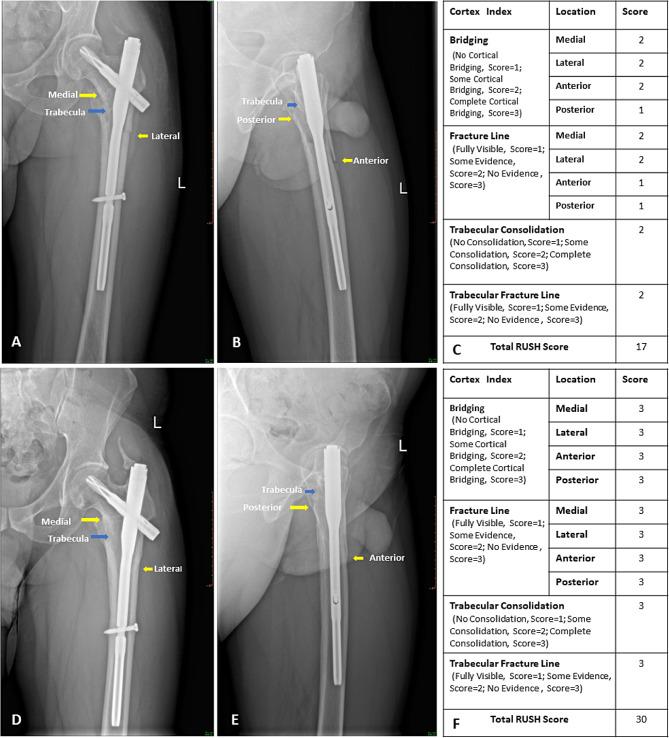

We obtained 94 sets of X-ray films from the postoperative follow-up of 35 patients who underwent intramedullary nail fixation for subtrochanteric fractures. Six orthopedic trauma surgeons evaluated the imaging data and determined fracture healing based on subjective judgment. They then scored the X-ray images using the RUSH form. After four weeks, the same observers re-evaluated 47 randomly selected sets of radiographs. Subsequently, the observers and study designer conducted a consensus meeting where they agreed on whether the fractures had healed. We used Fleiss kappa to evaluate agreement among observers based on subjective impressions, and the intraclass correlation coefficient assessed RUSH score consistency. Regression analysis examined the relationship between scores and fracture healing consensus using a receiver operator characteristic (ROC) curve.

Based on overall impressions, the agreement level among orthopedic trauma surgeons for determining the healing status of subtrochanteric fractures was moderate (Kappa = 0.564, 95% CI: 0.511-0.616). However, utilizing the RUSH scoring system can improve the consistency to a substantial level of agreement (ICC = 0.748, 95% CI: 0.663-0.817). Regarding intraobserver reliability, there were significant differences among orthopedic trauma surgeons in judging fracture healing based on overall impressions. However, using the RUSH scoring form, the attending group achieved better intraobserver consistency than the resident group. Regression analysis and ROC curve analysis revealed a strong correlation between the RUSH total score, cortical bone score, cancellous bone score, and consensus on fracture healing. The AUC values are 0.769 (95% CI: 0.670-0.868), 0.779 (95% CI: 0.681-0.876), and 0.771 (95% CI: 0.674-0.867), respectively.

Our study highlights the effectiveness of the RUSH scoring system in enhancing interobserver agreement and intraobserver consistency when evaluating subtrochanteric fracture healing in orthopedic trauma surgeons. We propose setting 21 points as the threshold for the simplified RUSH scoring system to determine fracture healing. This system includes only eight items related to cortical bone, with a total score of 24 points.